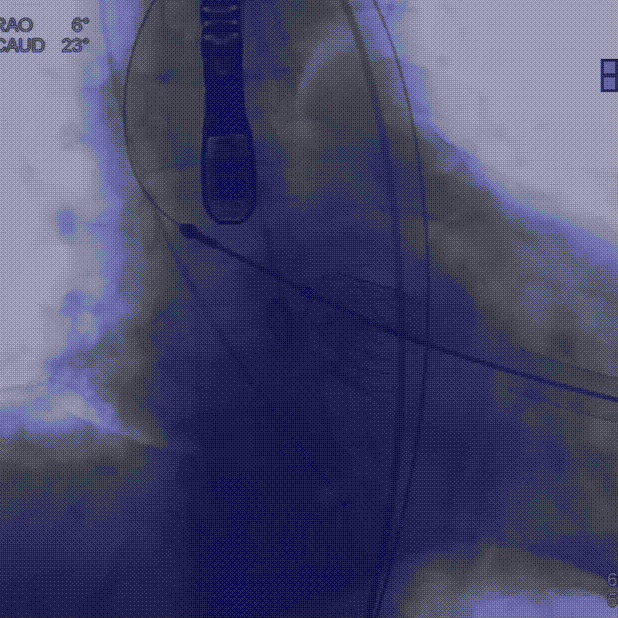

定位件入窦后造影:

降落瓣膜件:

140bpm快速起搏下释放瓣膜:

复查根部造影,未见明显反流: